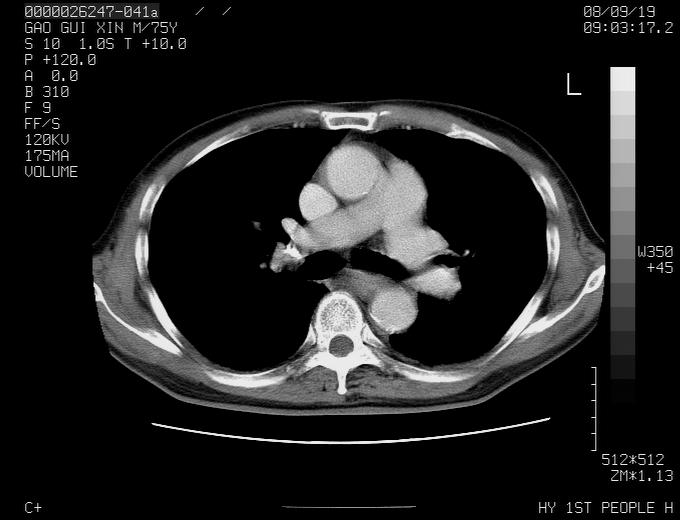

右上肺可见条索状影,并可见钙化,左上肺结节可以考虑为结核球,但气管前腔静脉后有肿大淋巴结,本人觉得左上肺结节不能排除转移瘤的可能,右上肺为陈旧性结核灶。

左肺上叶周围性肺癌并纵隔多组lnm.不可能是tb.

左肺上叶尖段瘢痕癌并纵隔淋巴结转移解释更好一些.

左肺周围癌并纵隔淋巴结转移,另一小结节是血管影

左上肺周围型肺癌并纵隔淋巴结转移

1)左肺上叶尖段周围型肺癌并纵隔淋巴结转移。2)冠状动脉及主动脉钙化。

左上肺周围型肺癌并纵隔淋巴结转移。纤支镜检查